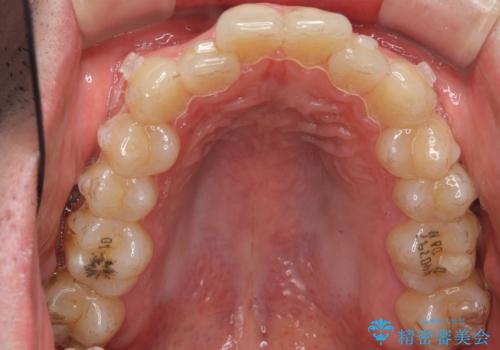

前歯のがたつき マウスピース矯正で 非抜歯で奥歯を後ろに下げる治療

- 前歯のがたつきを主訴に来院。

歯を抜かずに、奥歯を後ろに下げ、歯の両側をわずかに削って並べました。

奥歯を後ろに下げるのに、上下左右に矯正用ミニスクリューを入れています。

そのまま並べると戻りやすいのと、口元が出てしまうためです。

削る際も、拡大鏡を用いて精密に行っております。肉眼で削るのとは実は大きく差があります。